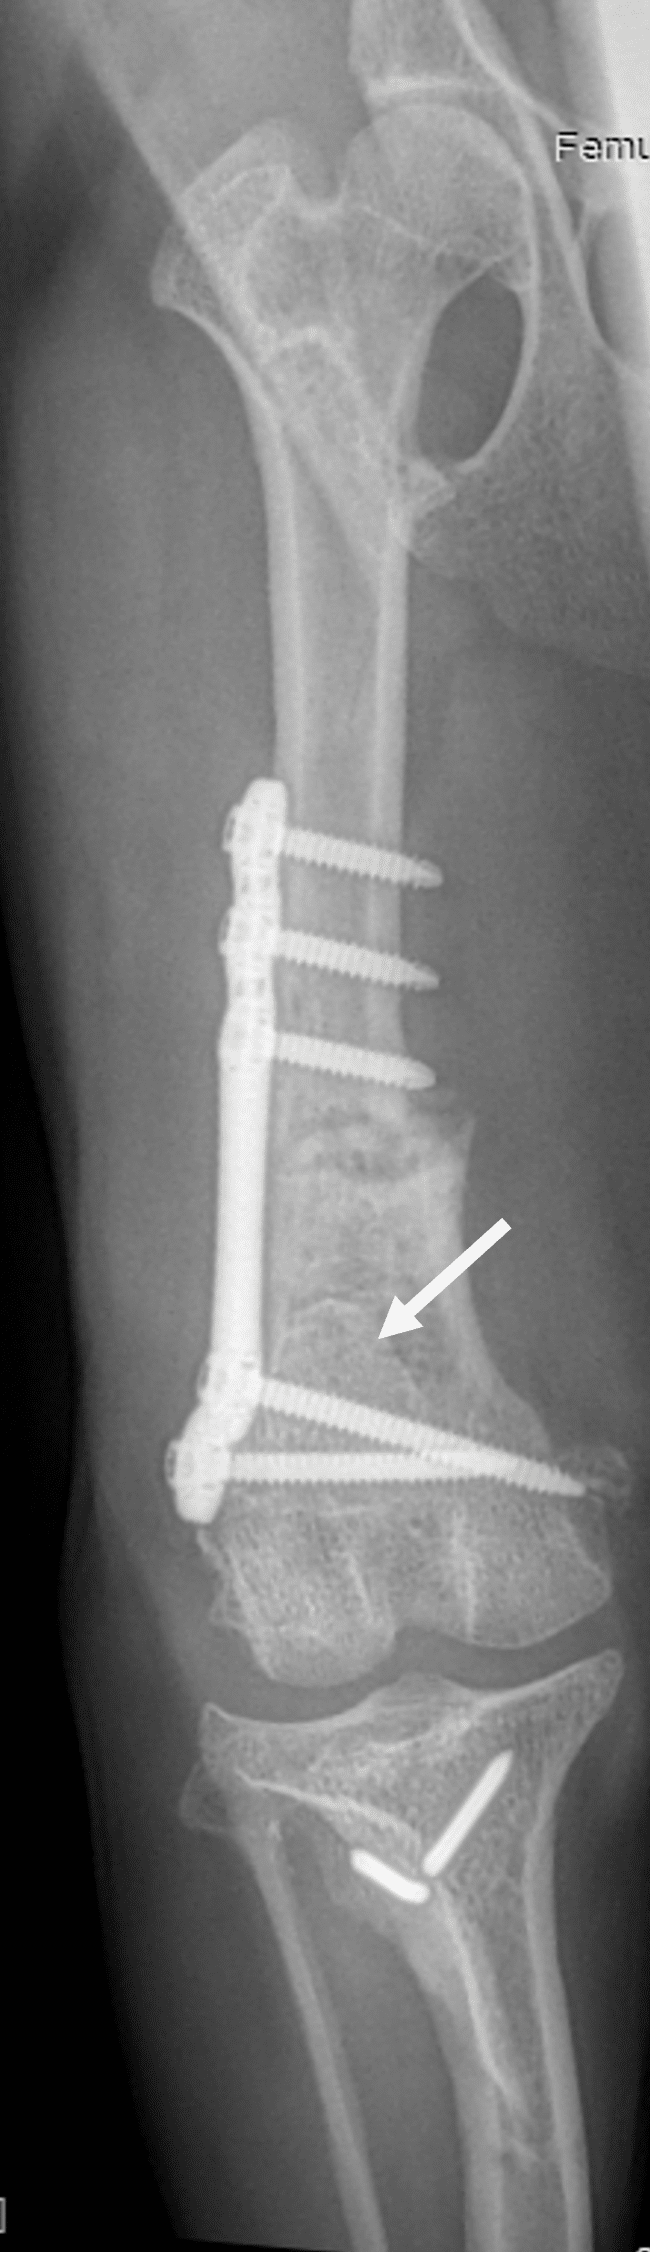

Lors de la chirurgie, plusieurs gestes sont réalisés conjointement. Les objectifs sont multiples : réaligner l’appareil extenseur du genou, recreuser la trochlée sans abimer le cartilage, traiter les déformations éventuelles (qu’elles soient à l’origine de la luxation, ou secondaires à la luxation), traiter les lésions associées (une rupture de ligament croisé par exemple).

- Reconstruire, à l’aide de différentes techniques, les tissus mous péri-articulaires, distendus par la rotule a force de se luxer.

- Réaliser une transposition de la crête tibiale. L’objectif ici est de réaligner l’appareil extenseur en déplaçant l’attache du ligament patellaire vers l’intérieur ou l’extérieur. La crête tibiale (le relief osseux du tibia sur lequel est attaché le ligament patellaire) est alors sectionnée et détaché du tibia, décalé de quelques millimètres, et refixé au tibia à l’aide de broches.

- Creuser la trochlée (la fosse dans laquelle est contenue la rotule) afin que la rotule puisse coulisser profondément.

- Corriger les déformations osseuses par différentes techniques d’ostéotomies correctrices lorsque la rotule se luxe secondairement à des déformations du tibia ou du fémur.